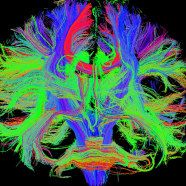

Some of my favorite scientific images to look at come from scanning the human brain with a tool called diffusion magnetic resonance imaging (or diffusion MRI). These images depict the long fibers that connect one part of the brain to another in a color-coded fashion, with a beautiful result: a colorful map of the brain’s structural highways.

I have always been drawn to the beauty of using the movement of water to recreate the fanning, tree-like architecture of the brain’s structural highways. I’m not the only one; the rock band Muse used an image generated from diffusion MRI as the cover art for their album “The 2nd Law” (below left). Aside from the colorful images produced by diffusion MRI, there is a simple beauty to the white matter itself. Artist and scientist Greg Dunn uses a technique called microetching to create stunning, reflective illustrations of human white matter. This image in particular (below right), part of a project called “Self Reflected”, shows how the axonal bundles branch out like a tree.